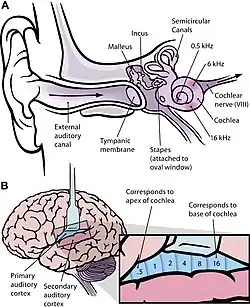

Hallucinoses auditives

L'hallucinose auditive est quasi similaire en mécanismes à l'hallucinose visuelle. Elle implique le système auditif et l’ouïe. Elle est une pseudo-hallucination auditive sans trouble de la conscience, ni participation affective du sujet.

- Les mécanismes de l'hallucinose auditive :

- Augmentation d’activité dans les régions temporales supérieures ou moyennes

- Hallucinose due à des lésions de la calotte pédonculaire, ou des liaisons thalamiques ou striato-capsulaires, ou aussi à des hémorragies.

- Ces illusions auditives dites hallucinoses auditives peuvent être entre autres :

- Des acouphènes, soit la perception de bruits parasites non réels

- Des hallucinoses musicales, telle la perception de musique malgré une surdité

- Des hallucinoses alcooliques auditives des buveurs de Wernicke

La paracousie, si elle est intense, est considérée comme une hallucination auditive ou hallucination sonore. Pour exemples, ce sont des patients qui entendent leurs propres pensées à haute voix, ou des patients qui perçoivent une ou plusieurs voix n'existant pas, ou des patients qui entendent une ou plusieurs voix lui dicter ses actions. Ces patients sont certains de la réalité de leur perception. Et ces patients montrent une activité cérébrale élevée impliquant notamment l'hypothalamus, et les régions para-limbiques.